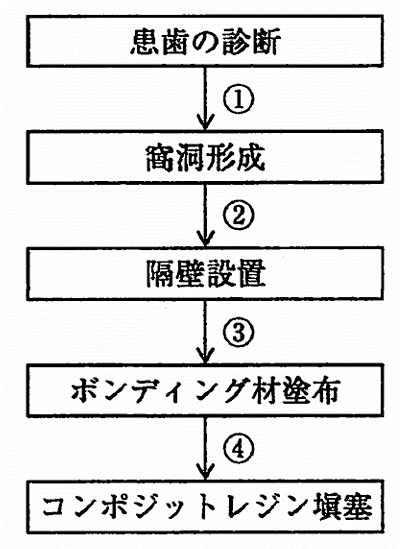

午前-38

下顎右側第一小臼歯遠心面のう蝕に対して、コンボジツトレジン修復を行うことになった。治療過程を図に示す。プレウエッジテクニックのウエッジの挿入時期はどれか。1つ選べ。

a. ①

b. ②

c. ③

d. ④

解答を見る

a